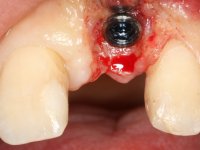

Female patient, 30 years old, non-smoker. The patient appeared in consultation after orthodontic treatment and placement of an implant at tooth site 2.1. Teeth 3.7, 3.6 and 4.7 had root canal therapy and teeth 1.5, 2.5, 2.6 and 4.5 had undergone extensive restorations. Patient had a thin periodontium and showed a satisfactory oral hygiene. After surgical exposure of the implant, it proved to be positioned improperly. Prosthetic rehabilitation of the implant proved impossible by adopting acceptable aesthetic criteria. The patient carried an acrylic temporary crown on a stump screwed as a fallback solution for six years, as she had not accepted the offer to remove the implant. After this time, patient returned to consultation with an abscess in tooth 1.1. After analyzing the situation, it was verified that teeth 1.1 and 2.2 had indicated extraction and the implant should be removed or submerged.

In the initial phase, it was proposed to the patient to perform the surgical implant exposure and after clinical evaluation, make prosthetic decisions. Once the healing screw was placed and the soft tissues were healed, an inadequate position of the implant was found. In view of the dramatic situation, the patient was proposed to remove the implant and put a new one after tissue regeneration. This proposal was rejected by the patient, who suggested temporary rehabilitation of the current implant. A new proposal was then made, to rehabilitate the implant, consisting of a screwed abutment, and on this, the placement of an acrylic crown with coronal and gingival components. After 6 years with the provisional treatment, the patient appeared in consultation with an abscess in tooth 1.1. After clinical and imaging analysis, it was decided to remove teeth 1.1 and 2.2, submerge the implant, place two implants at the site of 1.1 and 2.2 and perform adequate tissue regeneration. Temporization would be done with a provisional 3-element bridge, adhered with a net to the neighboring teeth. After osseointegration, definitive rehabilitation would be done with a 3-element bridge, including zirconia infrastructure and ceramic cover.

The surgical implant exposure and the healing screw placement proved to be a negative surprise regarding its position. Since the proposed removal of the implant was refused, we advanced to its provisional rehabilitation. An open tray impression technique was done, and a screwed abutment with a coronal and gingival component and an acrylic crown were made in the laboratory, using these two components. The provisional crown was placed in the mouth until a final decision was made. Six years passed before the patient returned to the clinic with an abscess on tooth 1.1. The choice to remove teeth 1.1 and 2.2 was made, to create a provisional 3-element bridge with a net to be adhered to the adjacent teeth. Surgery was planned and performed, placing the two implants at the site of 1.1 and 2.2, and the implant at the 2.1 site was cut with the objective of submerging it, while adequate tissue regeneration was performed (Surgical Work performed By Dr. Manuel Neves). During osseointegration, the patient used the fixed provisional bridge. A first impression was made for confection of a zirconia screwed provisional bridge, which worked the soft tissues for twelve weeks. The definitive impression was made with the individualisation of custom impression copings. Final rehabilitation was done with ceramized abutments, and also a bridge with zirconia infrastructure and ceramic cover. Due to the inclination of the implant placed at the site of tooth 1.1, the bridge required cemented fixation.